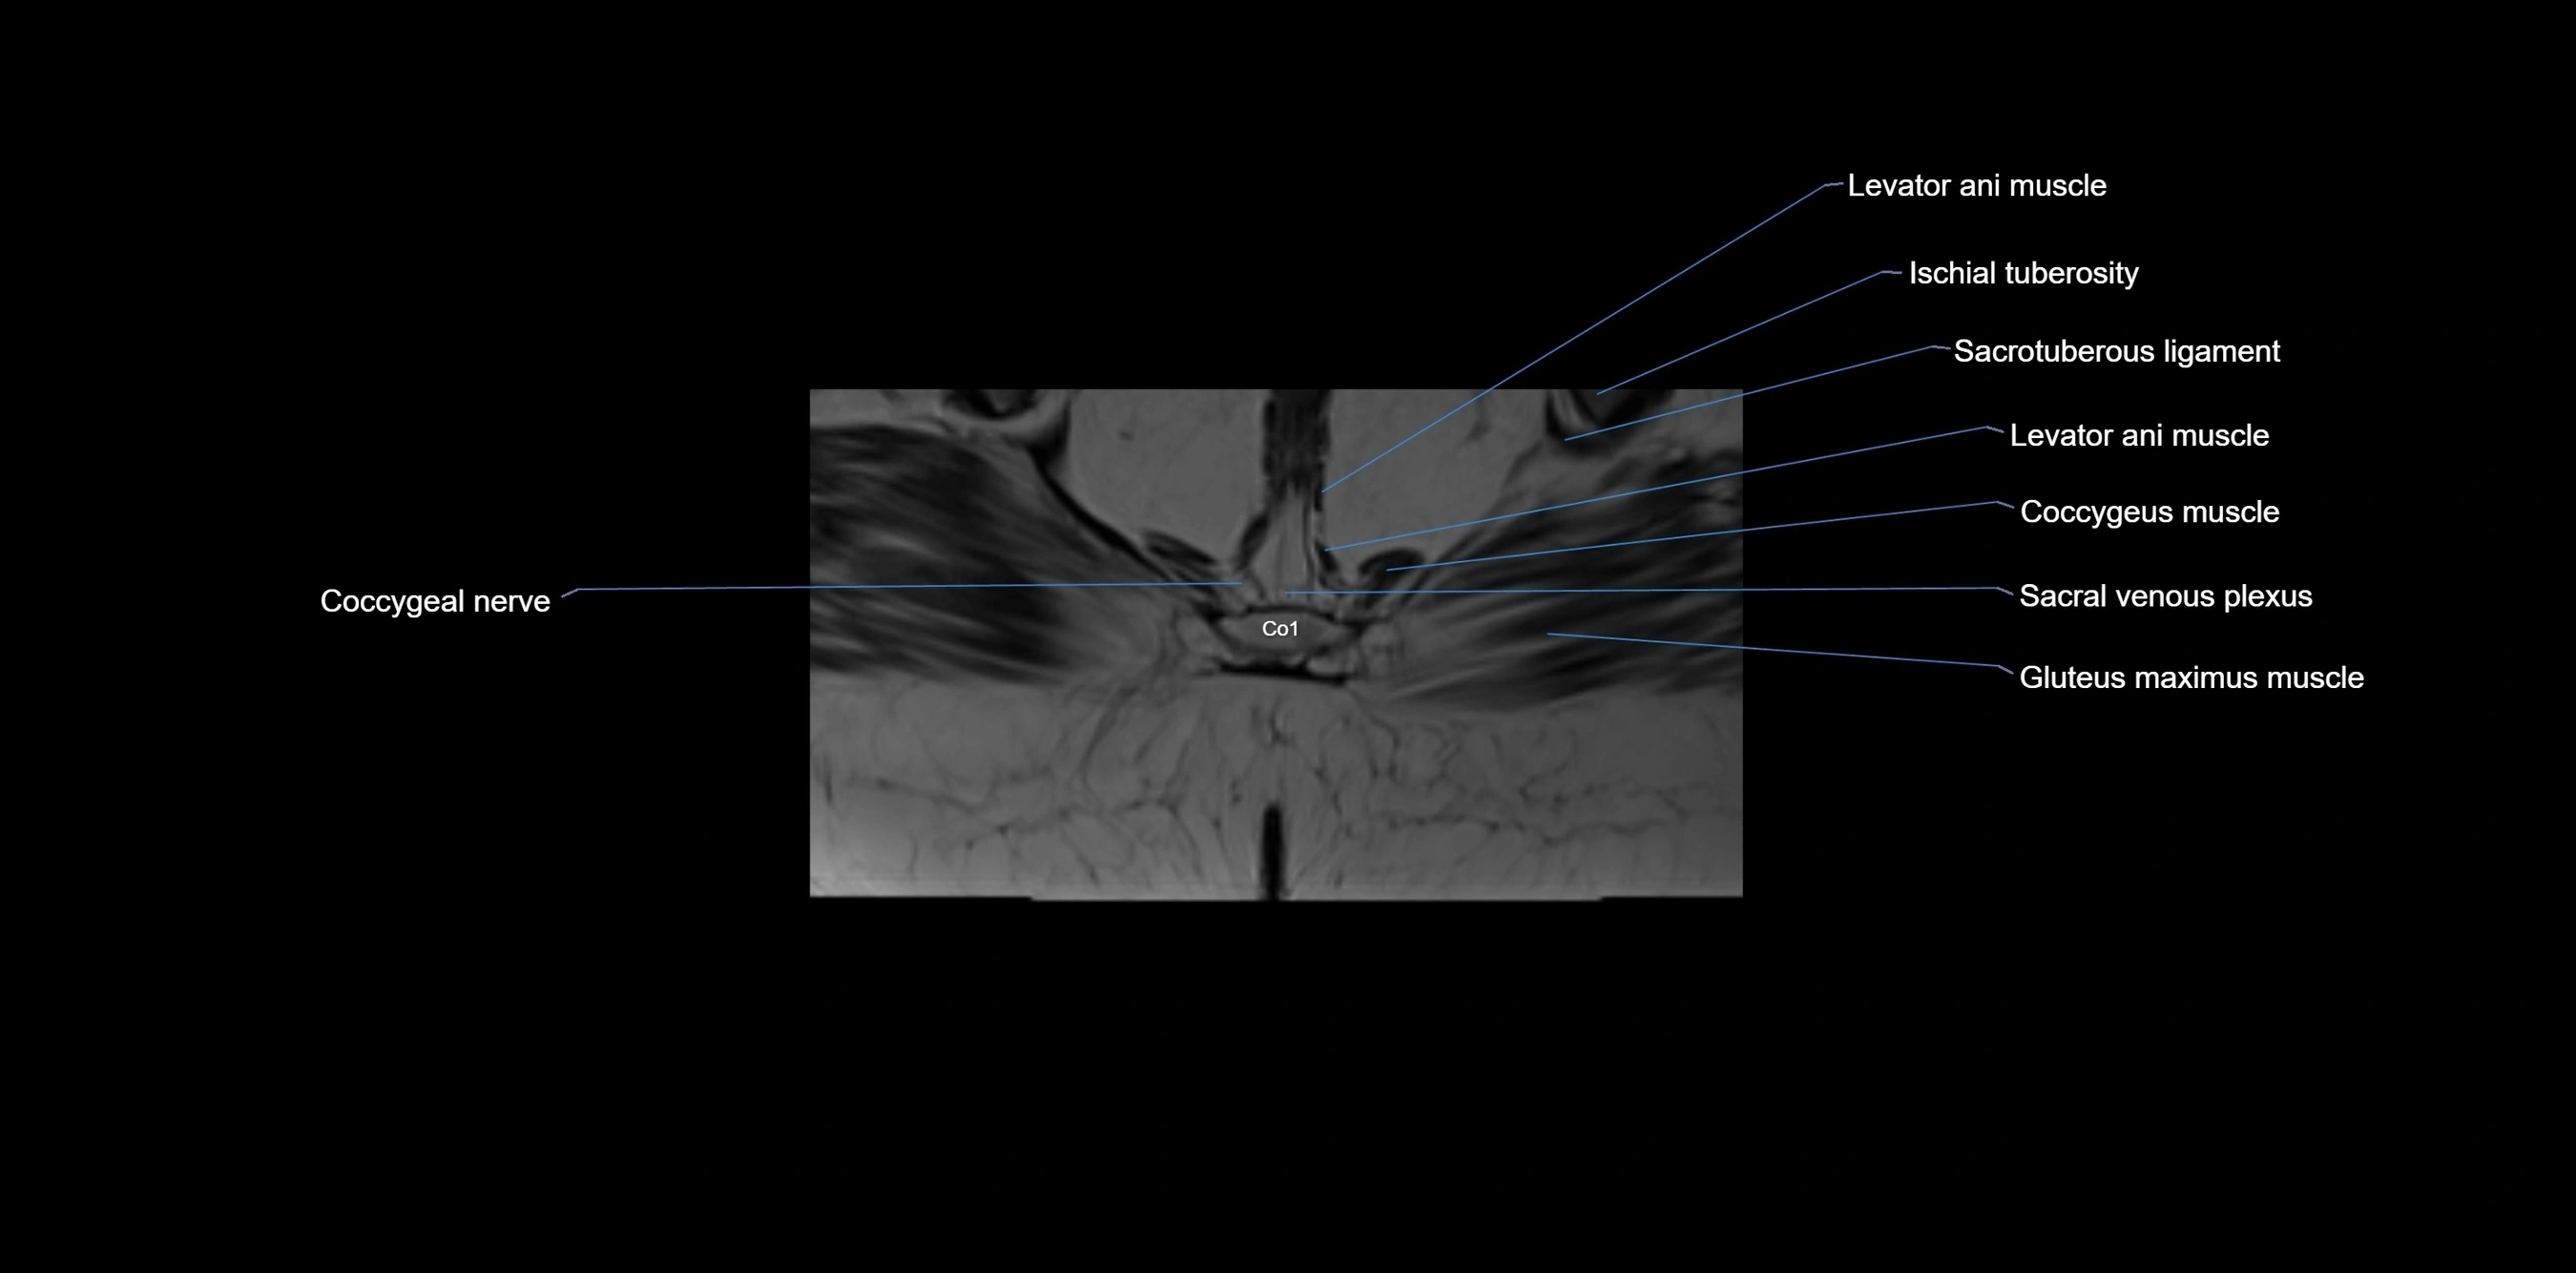

CT VRT image

image